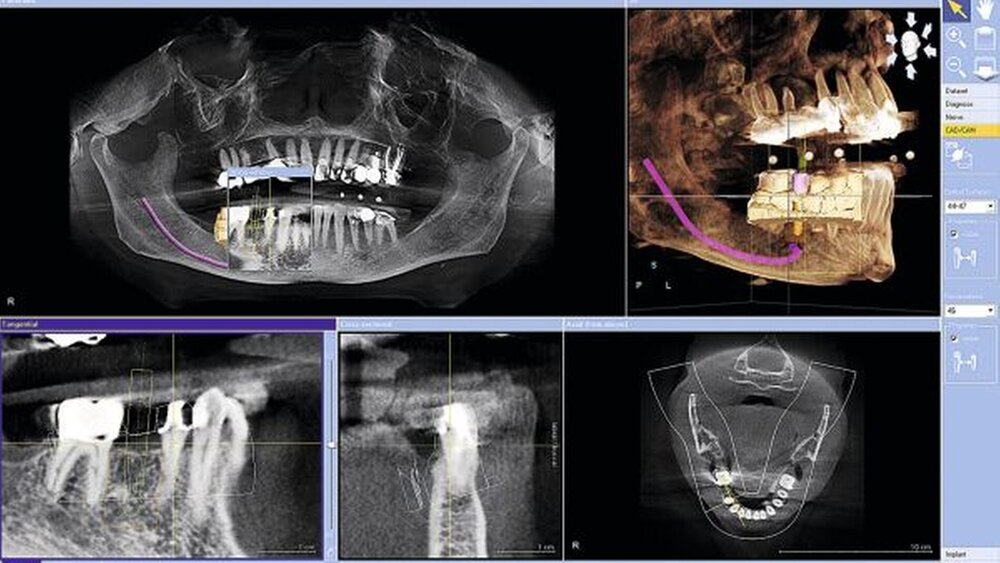

Digitale Volumentomographie und die virtuelle CAD-Konstruktion der Suprastruktur generieren zusammen eine prothetikbasierte Bildaussage für die Implantation (Abbildung 3). Dr. Klaus Wiedhahn, Buchholz, beschreibt die strahlungsarme Befundung im 3D-Verfahren. Enossalpfeiler, Abutment, Implantatkrone und chirurgische Bohrschablone werden exakt dimensioniert und eingeplant. Die verzerrungsfreie, detailreiche DVT-Aufnahme erhöht deutlich die Sicherheit für die OP. Insgesamt wird erkennbar, dass die Digitaltechnik die Behandlungsleistung des Zahnarztes erheblich steigern kann.